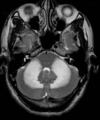

Qual o padrão da imagem na AMS-C?

A

Atrofia de cerebelo (vermis) e tronco (principalmente ponte); Hipersinal T2 na ponte: Sinal da cruz na ponte (não patognomônico), perda da barriguinha da ponte, Hipersinal nos pedúnculos cerebelares médios;

Atrofia de múltiplos sistemas tipo C

Atrofia da ponte e dos pedúnculos cerebelares médios Atrofia de múltiplos sistemas